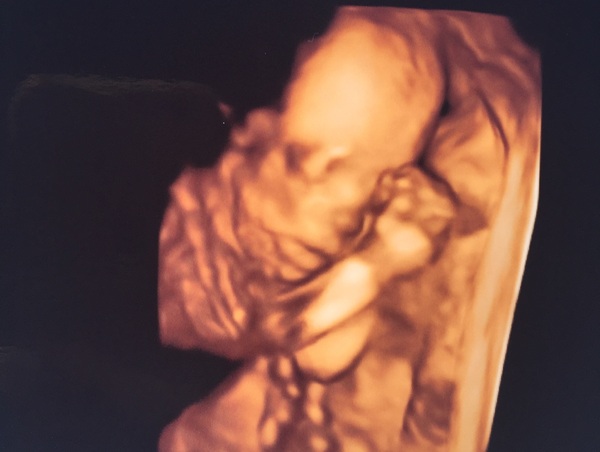

Haven't had a chance to catch up but baby Beanie is healthy and perfect and definitely a GIRLGrin we had to go private for this scan and the sonographer even gave us some 4D views. She's very cute if I do say so myself.

indi she is adorable!!! ❤

Indi yay for the definite girl. That scan is amazing Grin

indi oh she's so cute! What a little sweetie!